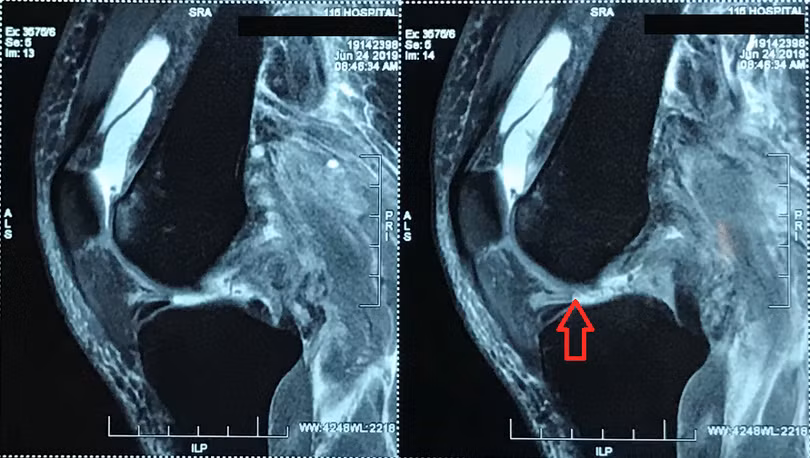

Tại Khoa Điều trị theo yêu cầu – Y học thể thao của Bệnh viện, kết quả chụp MRI khớp gối trái cho thấy, bệnh nhân đứt hoàn toàn đoạn gần dây chằng chéo trước, đứt hoàn toàn đoạn gần dây chằng chéo sau, đứt hoàn toàn đoạn gần dây chằng bên bên ngoài và bong gân độ I dây chằng bên bên trong.

![]() |

| Hình ảnh bị đứt nhiều dây chằng khớp gối trái của bệnh nhân trước khi mổ |